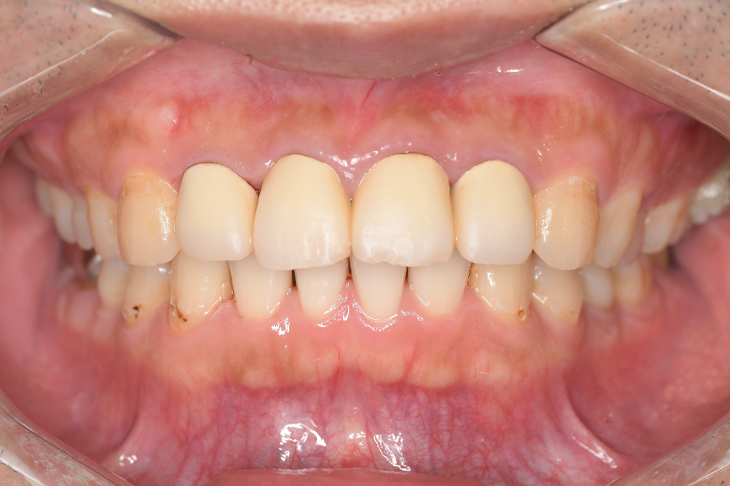

クリーニングの症例

現在の治療費と異なる場合がございます。最新の治療費は料金表をご確認ください。CASE 1

Before

After

基本情報

| 主訴 | 見た目をきれいにしたい |

| 治療期間 | 6ヶ月 |

| 治療費 | ジルコニアボンド(セラミックの被せもの)¥165,000×7(税込み) オフィスホワイトニング4回 ¥4,400×4(税込み) ホームホワイトニング¥11,000 |

| リスク・副作用 | かみ合わせがとても強い方の場合、稀に割れてしまうことがあります。 |

| 先生からの提案 | 上の前歯6本と右下の2番目の歯はセラミックの被せもので治療。 残りの下の前歯5本はプラスチックの材料で虫歯を治療し、 ホワイトニングをおこないました。白くなったご自身の歯の色に合わせてセラミックの 被せものを作成しています。 模型上で完成後をシュミレーションし、上の歯茎の位置をきれいに見えるように 揃えています。(外科処置はしていません) |